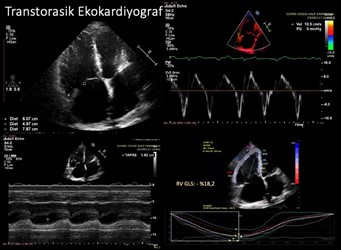

Sağ kalp boyut ve fonksiyonlarını değerlendirdiğimizde sağ ventrikül çaplarının oldukça genişlemiş olduğu (60*50*79 mm). Sağ ventrikül fonksiyonlarını temsil eden TAPSE ve RVS normal sınırlarda idi. Sağ ventrikül strain değeri ise -%18.2 olarak normalin (-%20) bir miktar altında olduğu tespit edildi (Resim-3).

Resim-3